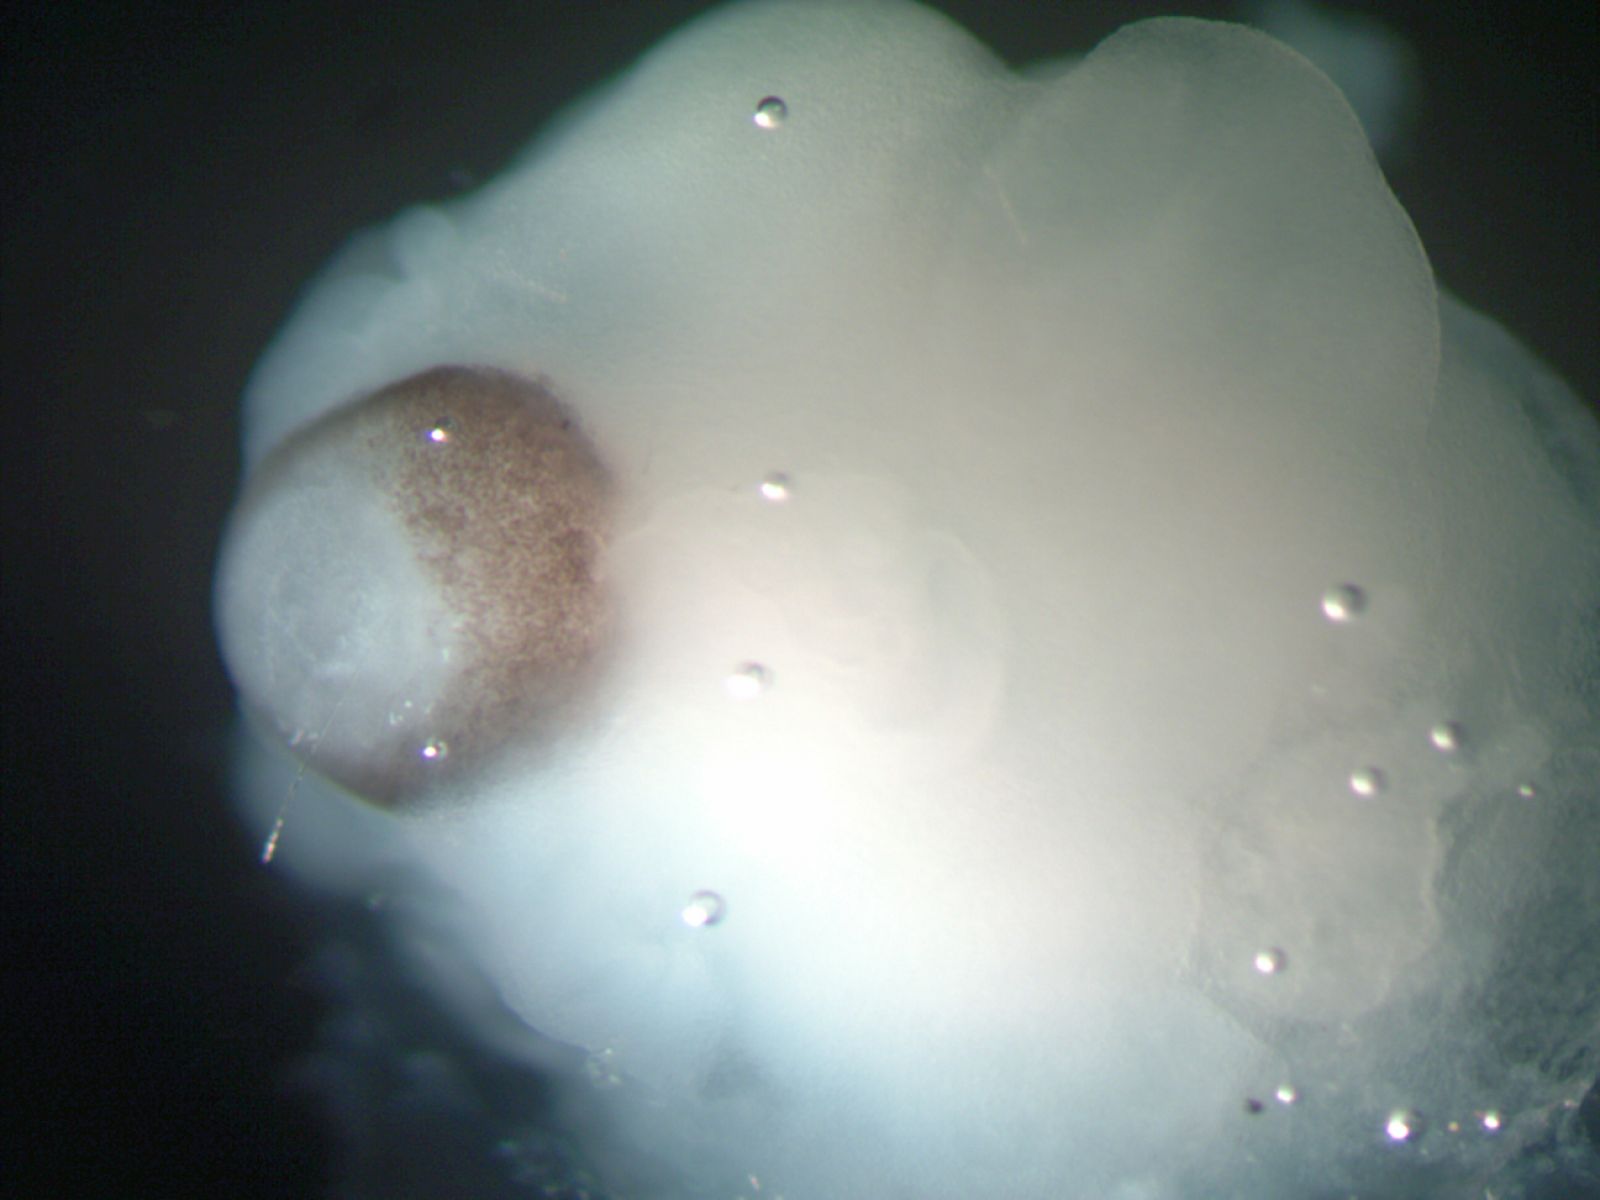

Mini cerebro con retina.

El órgano resultante fue un tejido continuo que rodeaba una cavidad llena de fluido que era una reminiscencia de un ventrículo cerebral. Al cabo de unos 20 o 30 días se desarrollaron regiones cerebrales definidas: córtex cerebral, retina, meninges y el plexo coroideo.